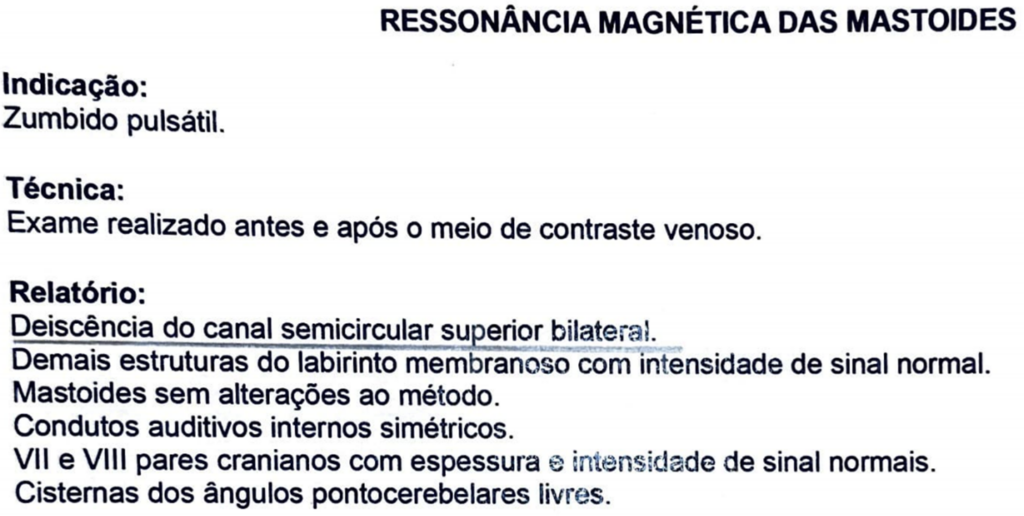

No exame de ressonância magnética da mastoide foi observado a presença de deiscência do canal semicircular superior bilateralmente. Na deiscência (Sindrome da Terceira Janela), costumamos observar esse diferencial aéreo-ósseo. Isso ocorre, porque parte da energia sonora transmitida através da janela oval “se perde” pela deiscência (via aérea), o que já não ocorre na via óssea.